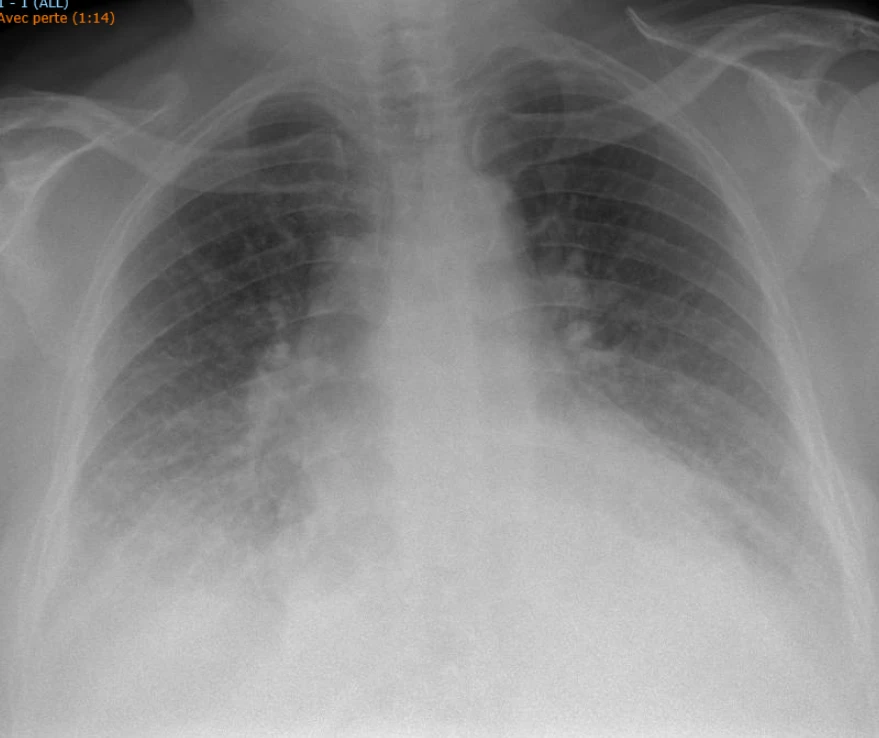

Une patiente de 70 ans connue pour une obésité et traitée pour un diabète sans insuline, consulte les urgences pour une dyspnée d’effort d’apparition progressive depuis quelques semaines, avec nette péjoration depuis 3 jours (actuellement NYHAIV). Elle décrit également une orthopnée nouvelle sans dyspnée paroxystique nocturne. Pas de douleurs thoraciques, pas de toux, pas de fièvre, pas de facteurs de risque thrombo-emboliques rapportés. Paramètres vitaux à l’arrivée : FC 70/​min, TA 135/​75mmHg, FR 13/​min, Saturation 94% sous 2L d’oxygène, T° 36.6. L’examen clinique met en évidence une patiente obèse, avec diminution du murmure respiratoire aux bases des deux côtés, pas de bruits surajoutés, et des œdèmes des membres inférieurs légers. Les mollets sont souples et indolore sans signes cliniques de TVP.Le laboratoire est sans particularité (Na, K, créat, CRP, FSS), tout comme l’ECG. Le NT-proBNP est normal (< 200 ng/​l).

Voici la radiographie du thorax :